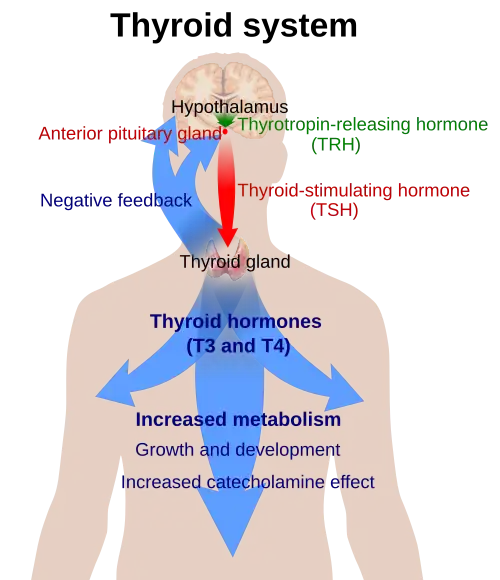

Hypothyroidism is caused by inadequate function of the gland itself (primary hypothyroidism), inadequate stimulation by thyroid-stimulating hormone from the pituitary gland (secondary hypothyroidism), or inadequate release of thyrotropin-releasing hormone from the brain's hypothalamus (tertiary hypothyroidism).[8][28] Primary hypothyroidism is about a thousandfold more common than central hypothyroidism.[11] Central hypothyroidism is the name used for secondary and tertiary hypothyroidism since the hypothalamus and pituitary gland are at the center of thyroid hormone control.

The thyroid gland is the only source of thyroid hormone in the body; the process requires iodine and the amino acid tyrosine. The gland takes up iodine in the bloodstream and incorporates it into thyroglobulin molecules. The process is controlled by the thyroid-stimulating hormone (TSH, thyrotropin), which is secreted by the pituitary. Not enough iodine, or not enough TSH, can decrease thyroid hormone production.[28]

The hypothalamic–pituitary–thyroid axis plays a key role in maintaining thyroid hormone levels within normal limits. Production of TSH by the anterior pituitary gland is stimulated in turn by thyrotropin-releasing hormone (TRH), released from the hypothalamus. Production of TSH and TRH is decreased by thyroxine by a negative feedback process. Not enough TRH, which is uncommon, can lead to insufficient TSH release and therefore insufficient thyroid hormone production.[11]